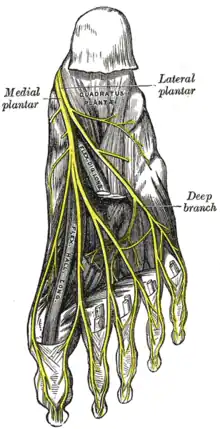

Innervation

Les nerfs du pied sont essentiellement issus du nerf sciatique dans la cuisse. Ce sont des branches des nerfs tibial d'une part, et d'autre part des nerfs fibulaire superficiel et fibulaire profond, issus du nerf fibulaire commun dans la jambe. Une petite partie de l'innervation est assurée par des branches du nerf saphène, issu du nerf fémoral dans la cuisse.

Le nerf tibial se divise en nerfs plantaire médial et plantaire latéral. Le nerf plantaire médial innerve quatre muscles : les muscles de la loge plantaire médiale ainsi que, parmi les muscles de la loge plantaire centrale, le court fléchisseur des orteils et le premier lombrical. Le nerf plantaire latéral innerve quatorze muscles : les muscles de la loge plantaire latérale, les muscles de la loge plantaire médiale à l'exception des deux cités précédemment et les muscles de la loge interosseuse. Les branches du nerf tibial innervent par ailleurs la peau du talon et de la face plantaire du pied.

Le nerf fibulaire profond innerve au niveau du pied un seul muscle, celui de la loge dorsale, et une petite partie de la peau du dos du pied. Le nerf fibulaire superficiel innerve la plus grande partie de la peau du dos du pied. Enfin, le nerf saphène innerve la peau de la face médiale du pied.